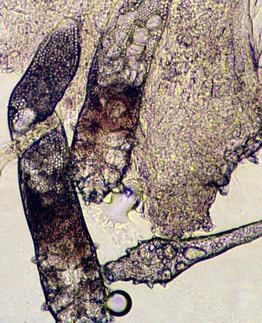

• In a touch prep, the base of a skin biopsy which includes dermis ± subcutis is tapped multiple times against a glass slide. After drying for several minutes, the glass slide is stained (e.g. Gram stain, Giemsa stain; Fig. 2.11).

Fig. 2.11 Microscopic examination of a ‘touch prep’ from an incisional biopsy performed of a necrotic lesion on the chest of an immunocompromised patient. Note the branching, ribbon-like, nonseptate hyphae characteristic of Rhizopus. Courtesy, Jean L. Bolognia, MD.